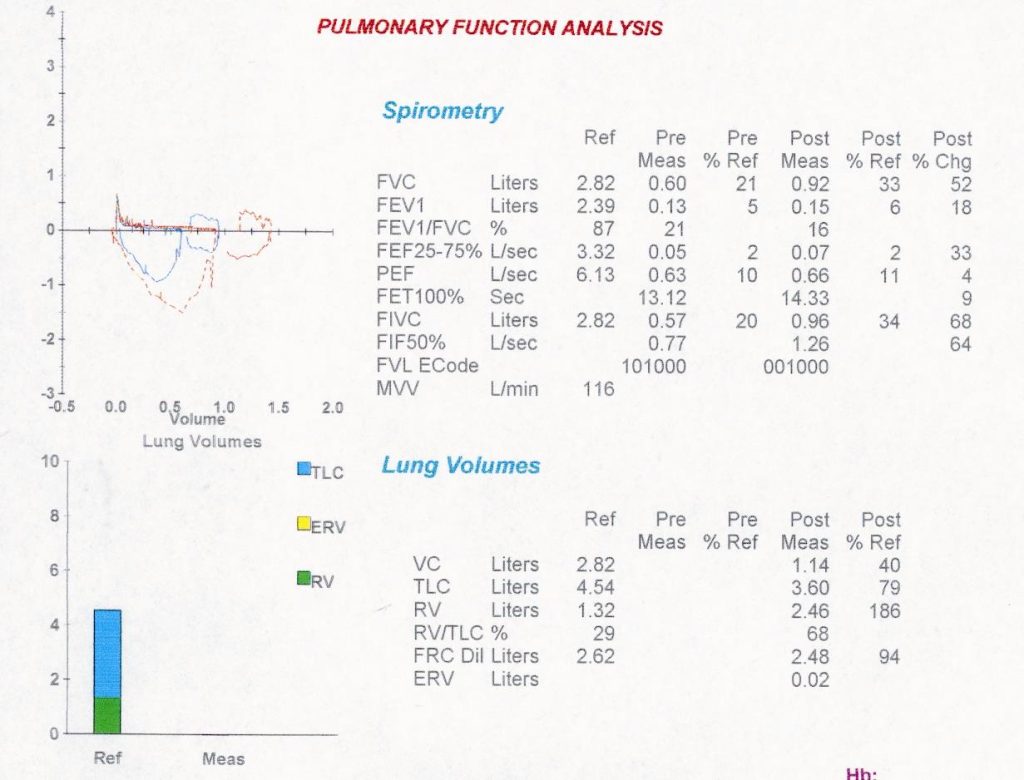

She defaulted follow-up but was readmitted again in October and November 2004 with similar symptoms. She was treated with bronchodilators and steroids and her symptoms seemed to improve. A pulmonary function test showed a severe obstructive ventilatory limitation with insignificant bronchodilator response.